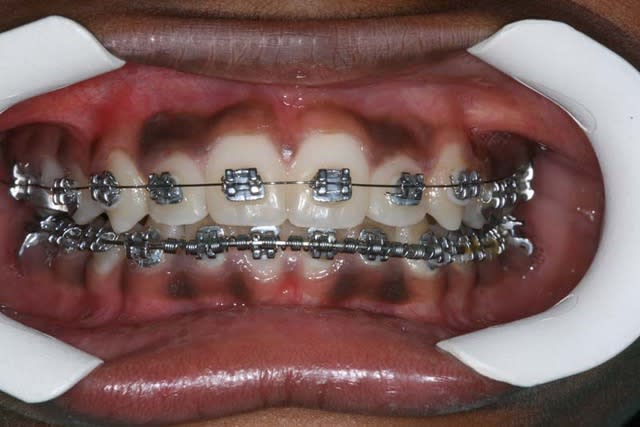

vous savez comme moi, que bouche ouverte, on a tendance à propulser, ce qui peut tromper sur mes photos

voici une photo bouche fermée du cas en cours, je n’en prends pas assez dans cette position

je peux vous en reprendre une, plus récente, si vous avez des doutes

voici les photos du m jour

bouche fermée

bouche ouverte

arcades

@+ Bjc.

Photo en occlusion prise aujourd’hui